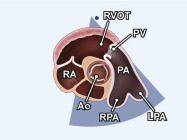

| 2.7. Mặt cắt trục ngắn cạnh ức (ngang mức các đại động mạch) khu trú vào van động mạch phổi

|

||||||||

|

|

Cửa sổ siêu âm cạnh ức Mặt cắt trục ngắn cạnh ức Xoay đầu dò 90O từ mặt cắt trục dài cạnh ức và ngửa đầu dò lên trên. |

Động mạch chủ (Ao)

Nhĩ phải (RA) Đường ra thất phải (RVOT) Van động mạch phổi (PV) Động mạch phổi (PA) Các nhánh phải (RPA) và trái (LPA) của động mạch phổi |

|||||